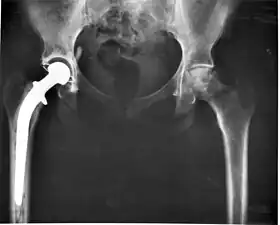

The modern total hip replacement was pioneered by Sir John Charnley, expert in tribology at Wrightington Hospital, in England in the 1960s.[10] He found that joint surfaces could be replaced by implants cemented to the bone. His design consisted of a stainless steel, one-piece femoral stem and head, and a polyethylene acetabular component, both of which were fixed to the bone using PMMA (acrylic) bone cement. For over two decades, the Charnley low-friction arthroplasty and its derivative designs were the most-used systems in the world. This formed the basis for all modern hip implants.

The Exeter hip replacement system (with a slightly different stem geometry) was developed at the same time. Since Charnley, improvements have been continuous in the design and technique of joint replacement (arthroplasty) with many contributors, including W. H. Harris, the son of R. I. Harris, whose team at Harvard pioneered uncemented arthroplasty techniques with the bone bonding directly to the implant.

Arthroplasty is an orthopedic surgery where the articular surface of a musculoskeletal joint is replaced, remodeled, or realigned by osteotomy or some other procedure. It is an elective procedure that is done to relieve pain and restore function to the joint after damage by arthritis (rheumasurgery) or some other type of trauma. As well as the standard total knee replacement surgery, the uni-compartmental knee replacement, in which only one weight-bearing surface of an arthritic knee is replaced, is a popular alternative.[27]

Joint replacements are available for other joints on a variable basis, most notably the hip, shoulder, elbow, wrist, ankle, spine, and finger joints.

In recent years, surface replacement of joints, in particular the hip joint, has become more popular amongst younger and more active patients.[28] This type of operation delays the need for the more traditional and less bone-conserving total hip replacement, but carries significant risks of early failure from fracture and bone death.

One of the main problems with joint replacements is wear of the bearing surfaces of components.[29] This can lead to damage to the surrounding bone and contribute to eventual failure of the implant. The use of alternative bearing surfaces has increased in recent years, particularly in younger patients, in an attempt to improve the wear characteristics of joint replacement components. These include ceramics and all-metal implants (as opposed to the original metal-on-plastic). The plastic chosen is usually ultra-high-molecular-weight polyethylene, which can also be altered in ways that may improve wear characteristics.